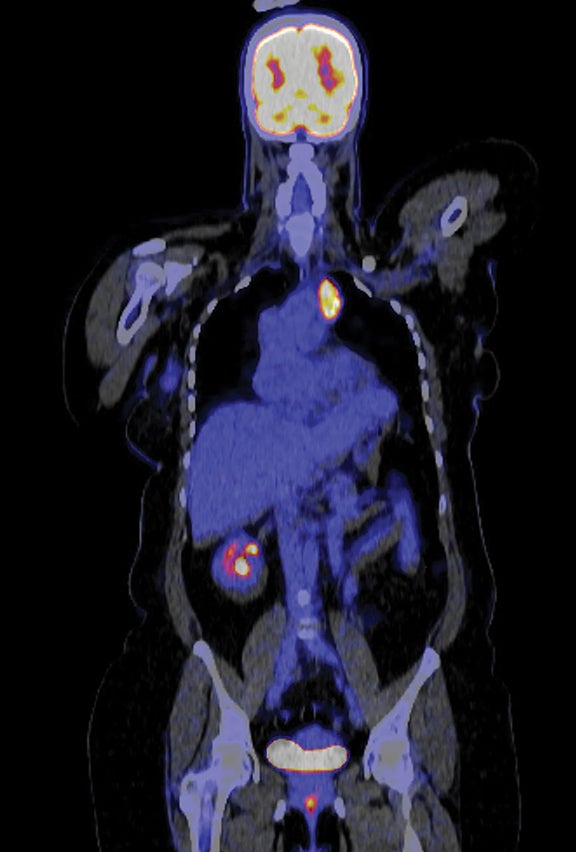

Case Report: Mediastinal Epithelioid Hemangioendothelioma in a Patient With Concurrent Early Stage Right Breast Cancer 💗🔗 ow.ly/88Kj50X8URp #BCAM25 #BreastCancerAwarenessMonth #WomensHealth #RadOncEd #MedEd